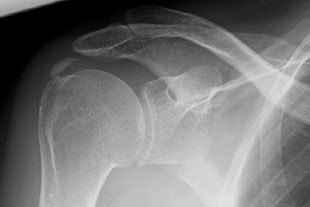

Im Röntgenbild und in der Sonographie des Schultergelenkes finden sich Kalkeinlagerungen, zumeist in der Supraspinatussehne (Teil der Rotatorenmanschette) von unterschiedlicher Beschaffenheit und in verschiedenem Ausbreitungsgrad.